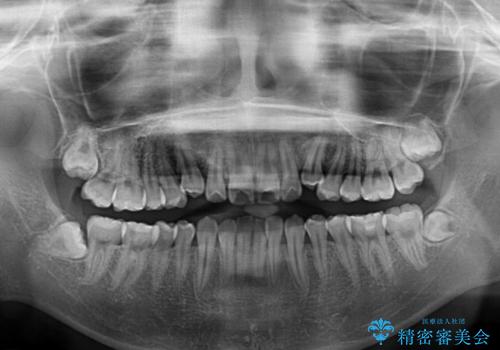

- 前歯の叢生と上顎左右の八重歯を気にして来院された患者様です。

奥歯の咬み合わせを見ると、左側は上顎が下顎に対して相対的に前方にあり、上下の前歯が接触していない状態でした。

咬み合わせを改善するためには、左側上顎臼歯を後方に移動させた咬み合わせにする必要があります。

インビザライン単体で改善することも可能性もありますが、インビザライン単体で達成する可能性が低いと考えられたため、カリエール・ディスタライザーという補助装置を併用して、より確実性を上げることとしました。